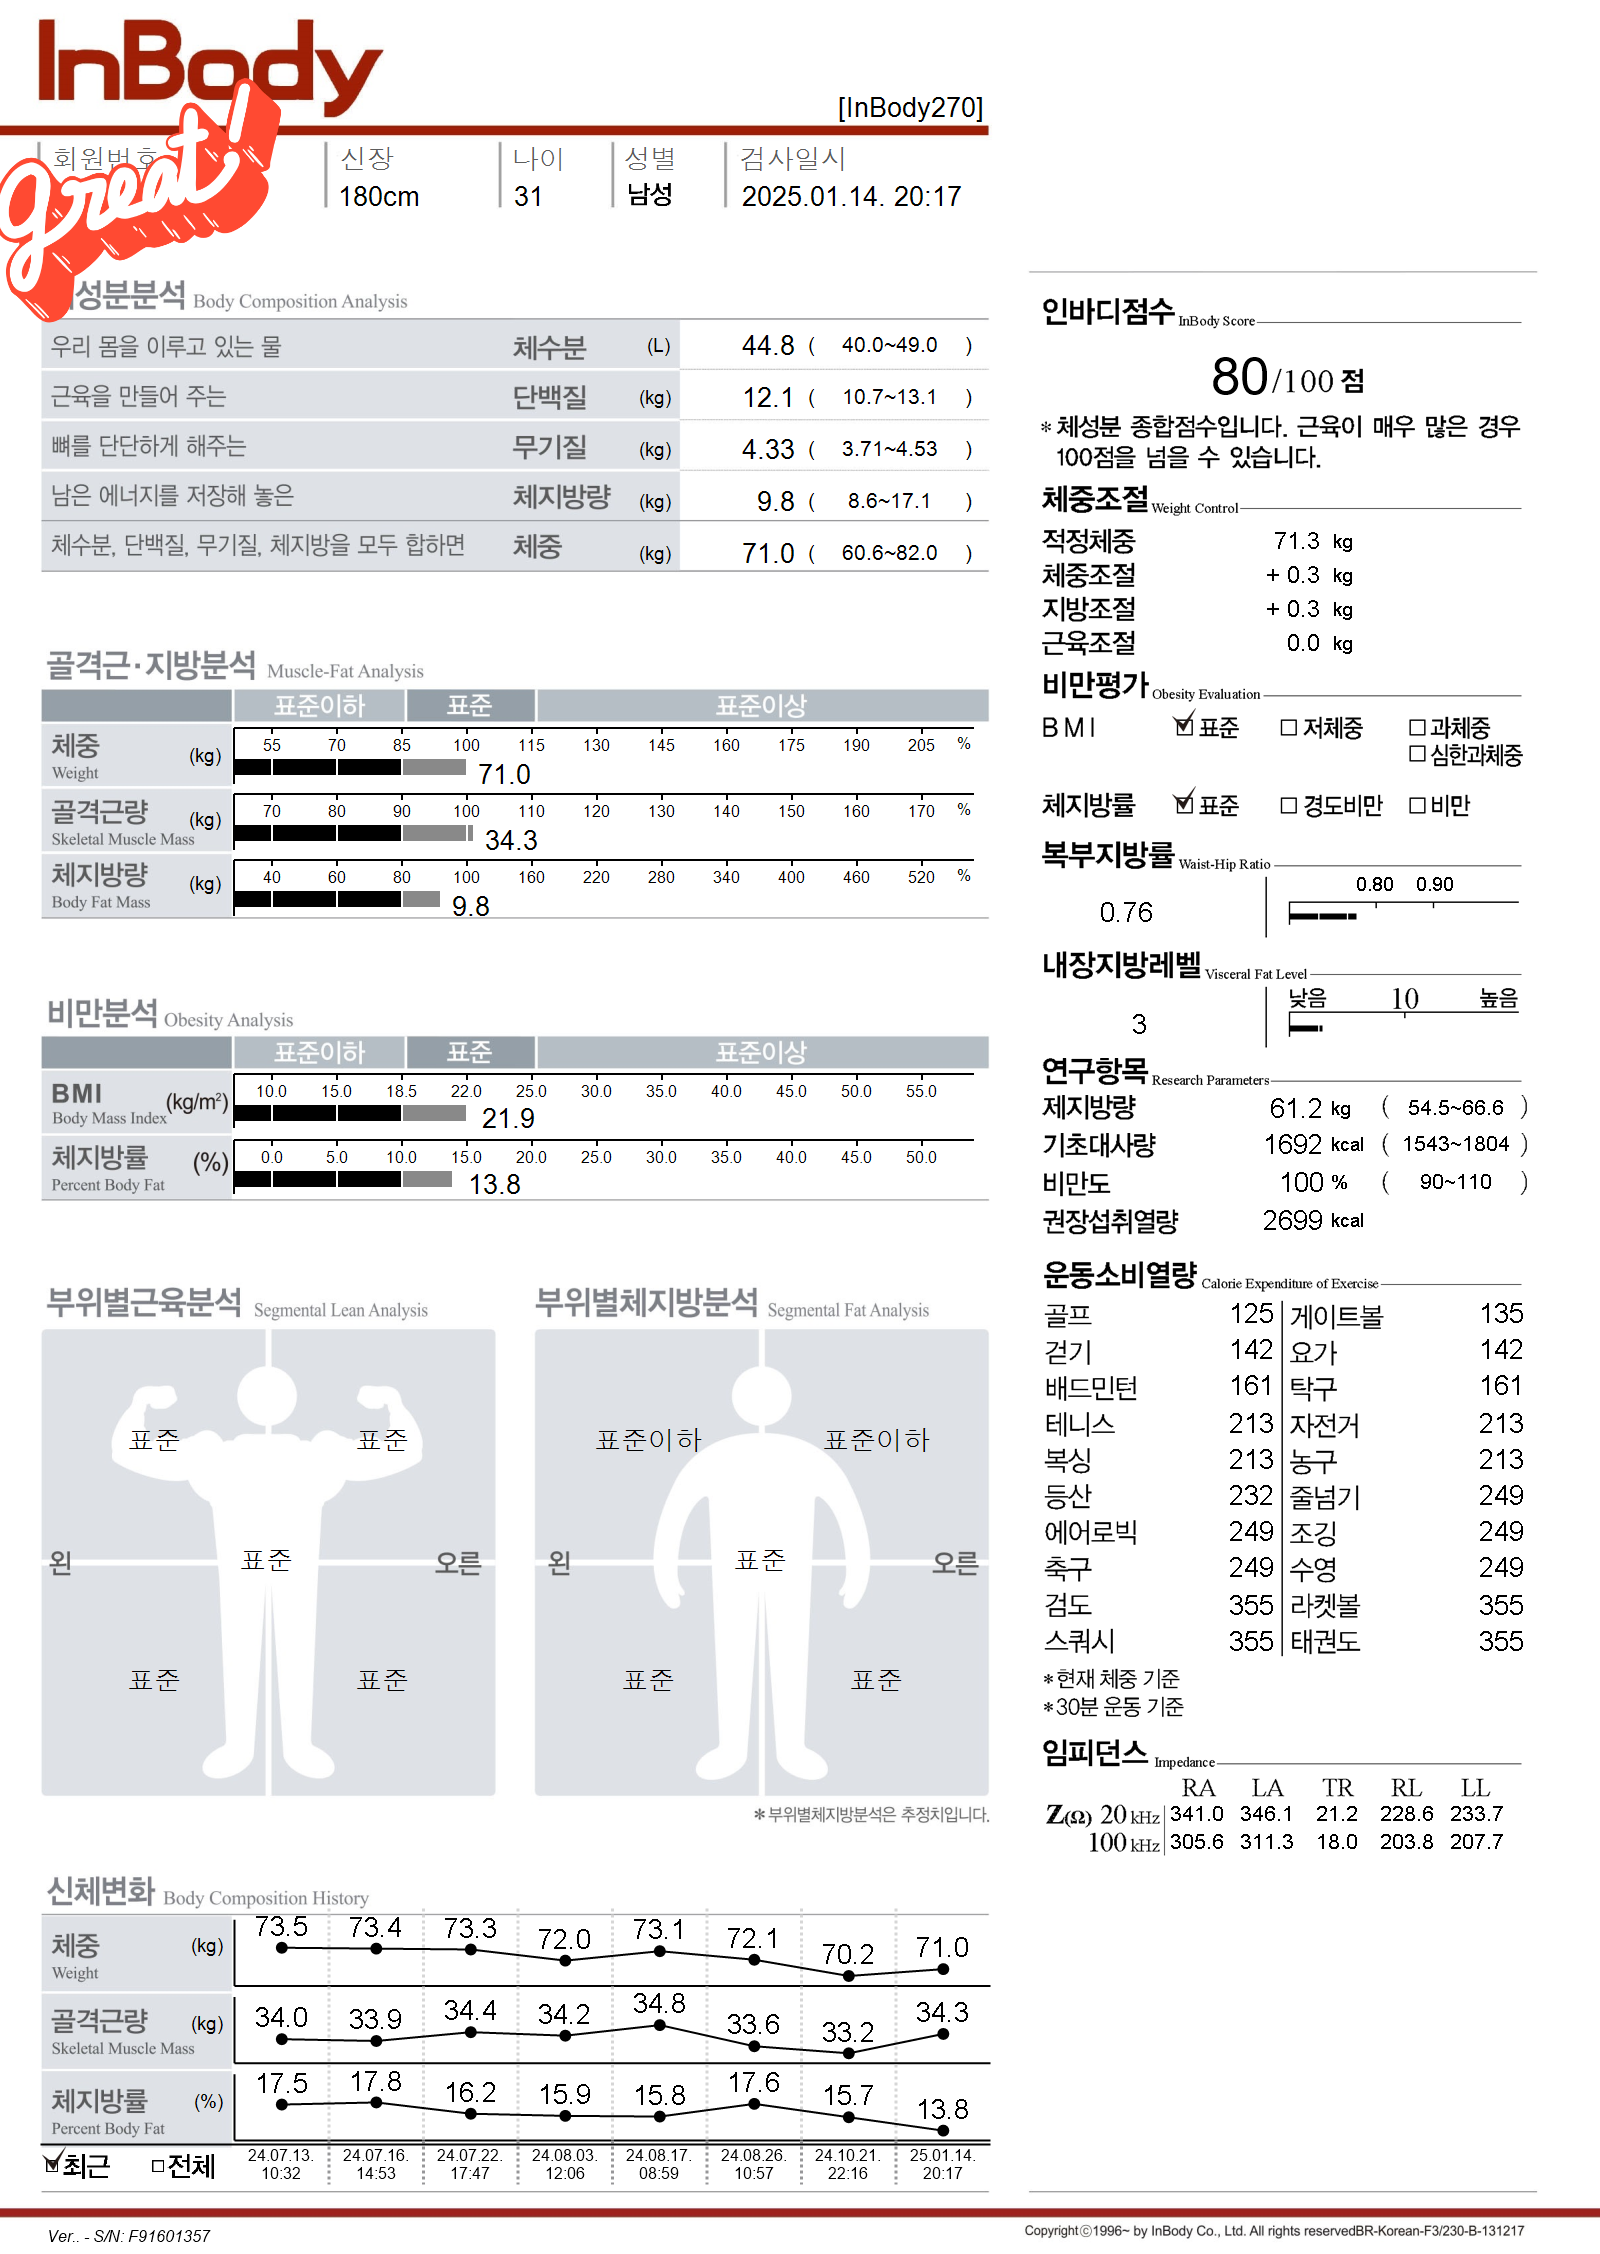

클라이밍 하다가 손목 다쳐서 쉬고..

헬스하다가 어깨 안좋아져서 쉬고...

인자약이라 슬펐지만 작년여름에 다시 해보자 으쌰으쌰해서 크로스핏 시작함

설렁설렁 하면서 안다친다는 마인드로 하는중...

그래도 몇년전에 비해 뱃살은 많이 줄은 것 같음 ㅋㅋㅋ

어제 인바디 재봤는데 마침 체지방률이 딱 27.7에서 13.8로 절반 되었길래 근황 올려봅니다..